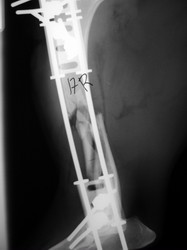

Fijación Externa

PRÁCTICAS CURSO DE FIJACIÓN EXTERNA PERFECCIONAMIENTO.

Húmero.